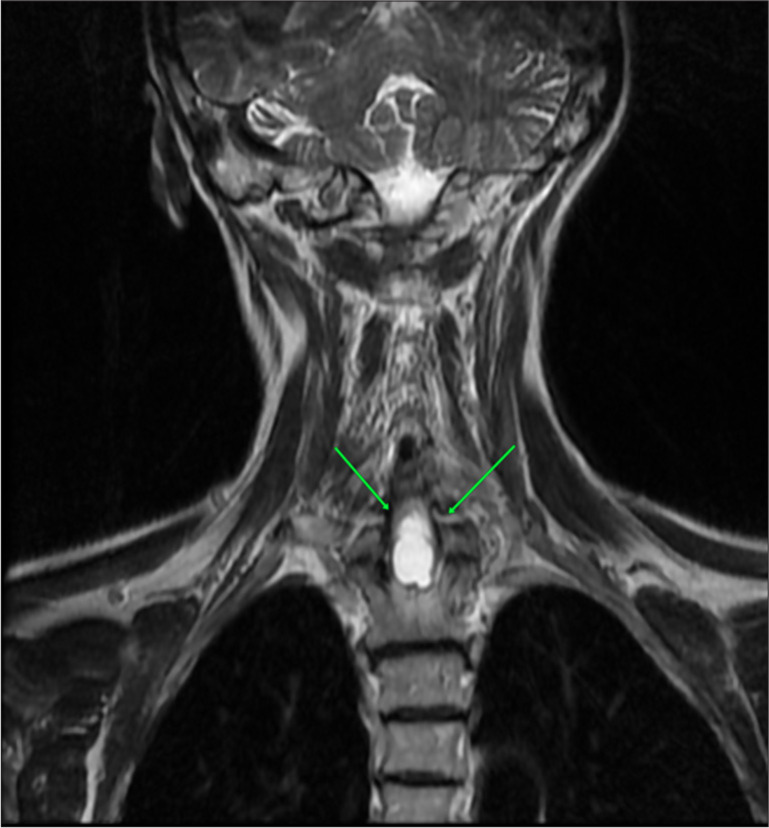

Syringomyelia is a rare condition characterized by the formation of a fluid-filled cyst within the spinal cord, leading to myelopathy. In addition, the pathological enlargement of the central canal is referred to as hydromyelia or cleft-like syrinx. We present a case of idiopathic syringomyelia and hematomyelia in a 50-year-old female patient with a 5-year follow-up on her disease progression. Magnetic resonance imaging (MRI) images revealed low-signal intensity on T1 and high-signal intensity on T2, with elevated hemorrhagic signal intensity on T1 and low peripheral signal intensity on T2. A fluid-filled lesion measuring 12 × 36 mm was observed between the C7 and Th3 vertebrae, with separation from some of the detailed components. No contrast enhancement was noted following IV contrast administration. Based on the MRI findings, a diagnosis consistent with giant hemorrhagic syringomyelia was established. Subsequently, a neurosurgical intervention was performed, resulting in a reduction in the size of the syringomyelia and a moderate improvement in the patient's symptom profile.